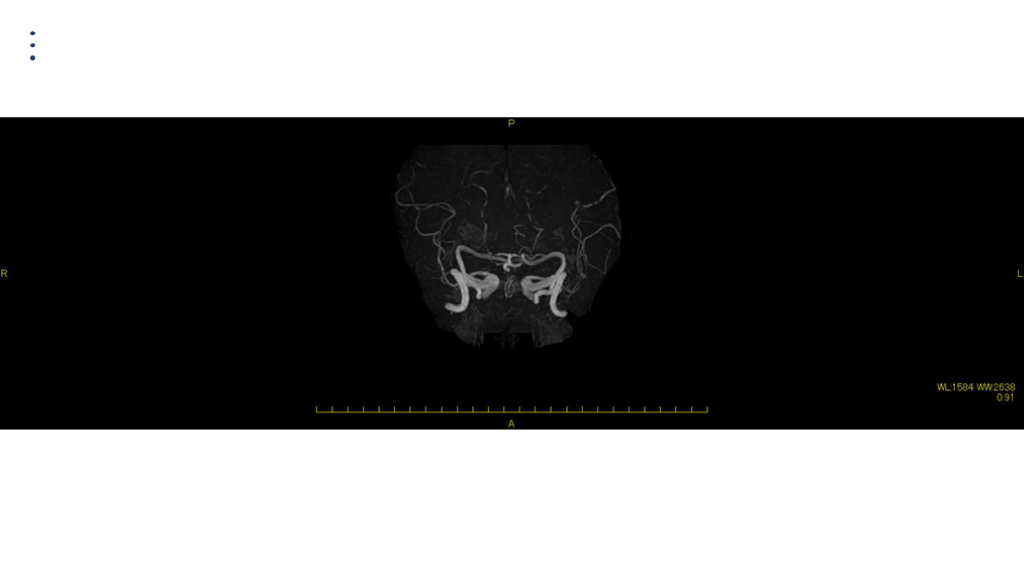

MRA DAY2

画像 所見 DAY 14 MRA 悪化